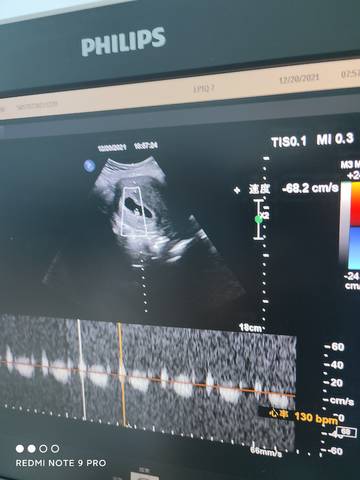

六周五天,胎芽胎心都挺好,就是不知道是男孩女孩,有会看的么?

journal_insert_pic_1683108714journal_insert_pic_1683108768

#妈妈问答大赛#胎心胎芽发育都挺好的,就可以了,没有必要太过纠结于性别,保持良好的心态吧!